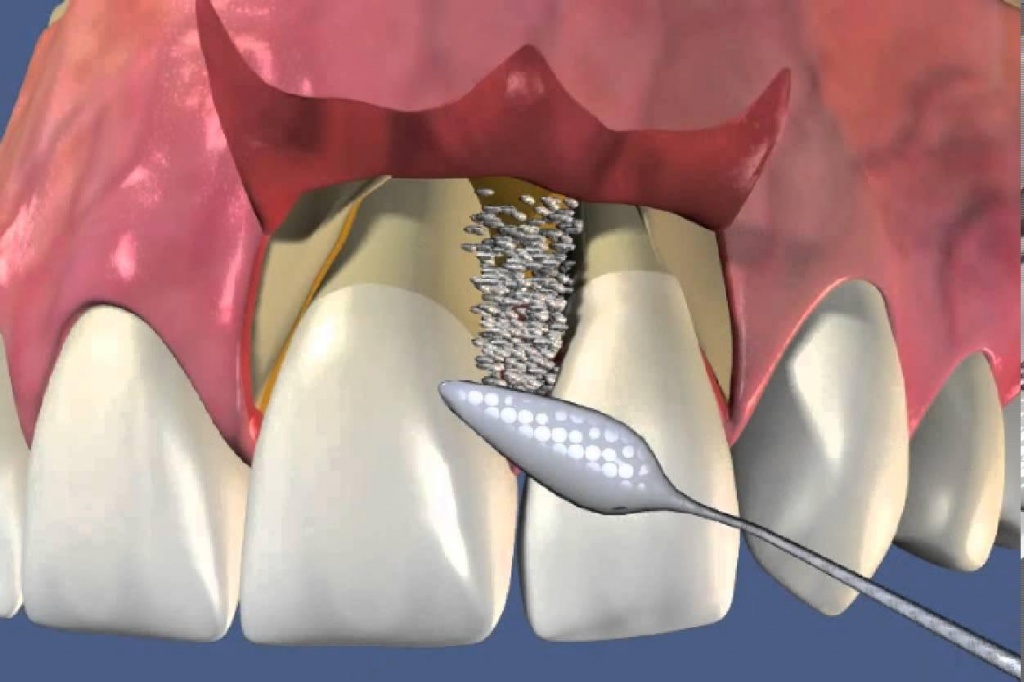

Реплантация зуба: Этапы и особенности операции